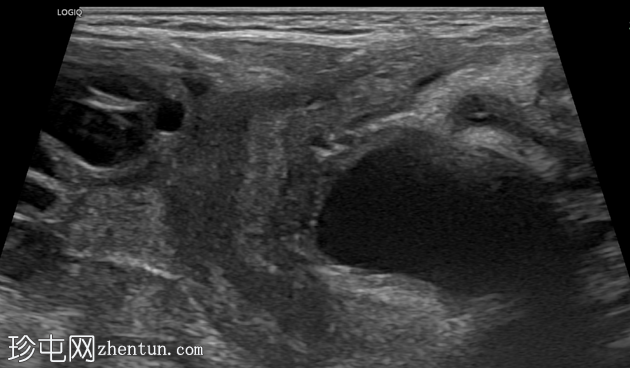

横切面

纵切面

右侧努克氏疝管长约6毫米,内含部分子宫和卵巢(大小约1.5 x 1厘米)。在整个检查过程中,这些组织均保持原位。

对侧附件呈多囊性改变,大小约3 x 1.8厘米。

膀胱外观大致正常。

上述超声特征清晰地显示了努克氏疝管的内容物及其延伸范围;其中包含患者的一侧卵巢和部分子宫组织。

这些特征符合卵巢努克氏疝的诊断。